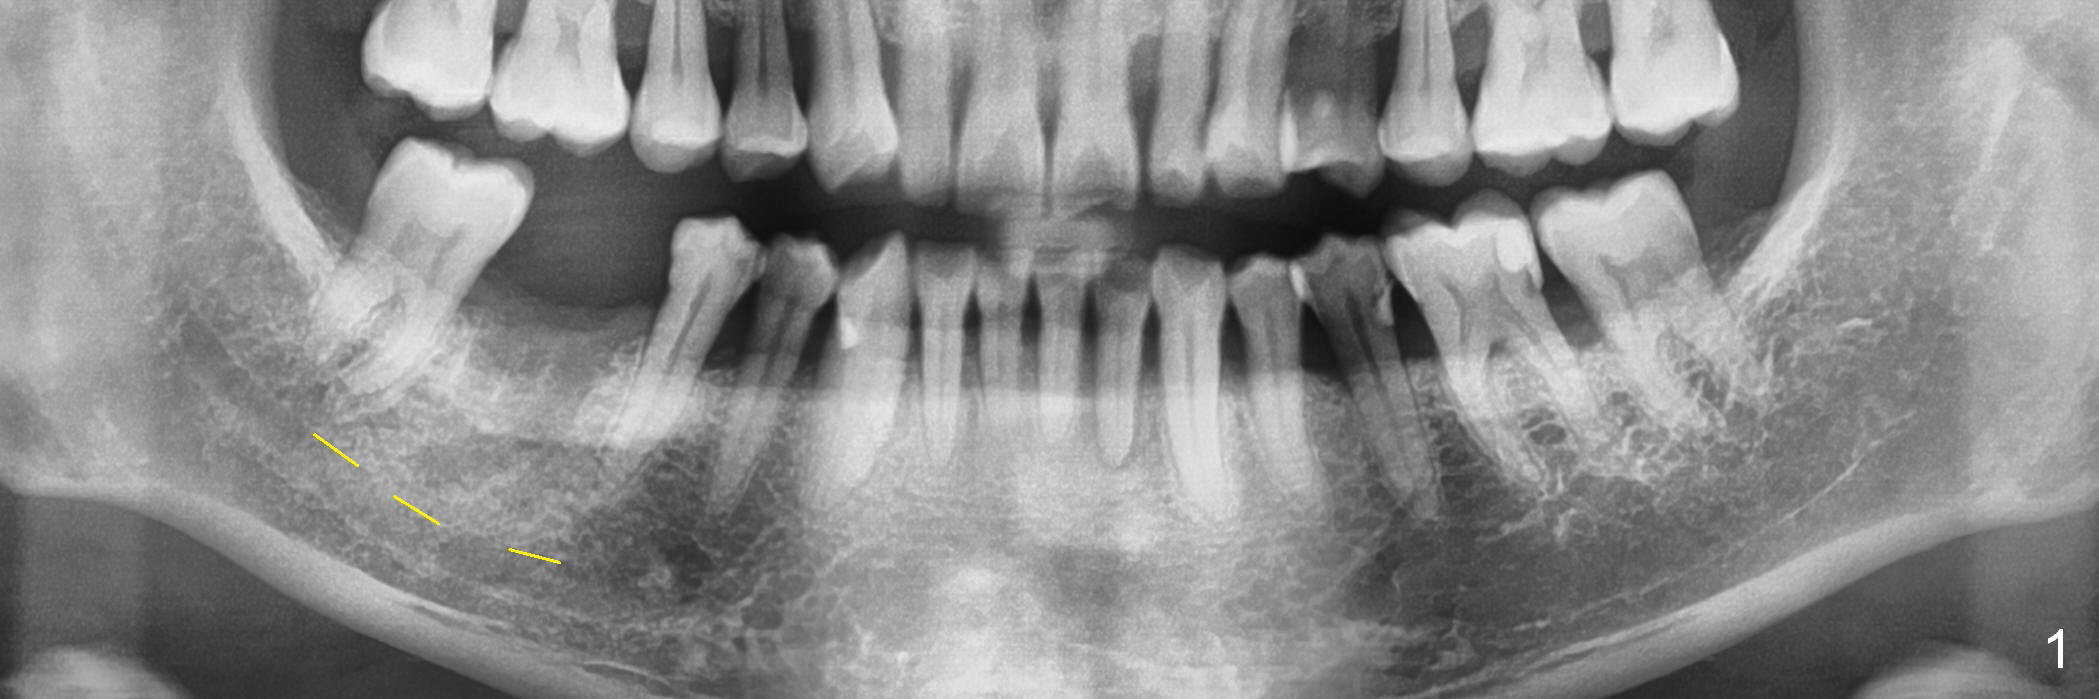

A 44-year-old man lost the tooth #30 three months ago. He is very nervous about the Inferior Alveolar Nerve (Fig.1,3 yellow dashed line). Offer Valium if needed. Check whether there is DO caries of the tooth #29 (Fig.2 <). Finish composite if indicated. There is mild to moderate buccal plate atrophy. The implant may have to be placed slightly lingually. When the insertion torque is high, place an abutment (Fig.3 white inverted cup) with subgingival margin (arrowheads: gingival margin) so that the emergency profile of the crown is better. Make an ideal immediate provisional with good emergency profile and place sutures. The mesial bone may have to be trimmed (Fig.4 red area) so that the abutment is able to be seated without interference. Take photo at each step.